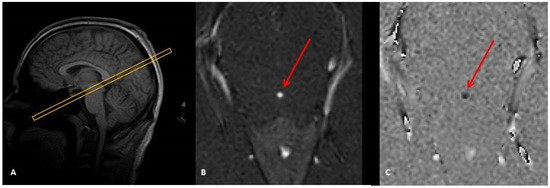

2.2. Image Acquisition